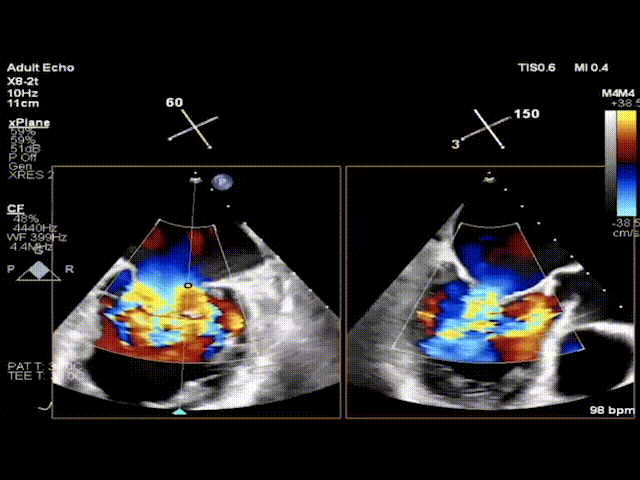

该例患者为74岁女性,因劳力性呼吸困难就诊,近期反复发作急性左心衰竭住院治疗,并伴有持续性房颤、高血压、糖尿病等疾病。超声心动图评估提示二尖瓣中重度返流、轻中度主动脉瓣返流与轻度三尖瓣返流,LVEDD 52mm,LVESD 40mm,LVEF 47%。二尖瓣返流机制为Carpentier I+IIIa型,有效返流口面积为0.31cm2,返流量47mL,瓣口面积为3.7cm2。因考虑外科手术风险高危,同时由于二尖瓣瓣口面积较小不适宜经导管二尖瓣缘对缘修复术,多学科团队讨论后决定使用Peijia HighLife TSMVR系统行经房间隔二尖瓣置换术。

术前,陈茂教授带领团队基于详尽的CT评估测量,判断评估患者术中风险并选择适合的手术策略。通过CT影像分割三维二尖瓣瓣环、测量其径线、计算二维投影径线并模拟植入HighLife TSMVR瓣膜,判断人工瓣膜与毗邻组织贴靠位置良好且无左室流出道梗阻风险。但该例患者二尖瓣装置结构较为特殊,存在风湿性病变所致腱索增粗、短缩、融合,为导丝成环步骤带来挑战,术中输送器需要始终保持合适深度,且导丝成环过程中需始终保持高位(靠近二尖瓣环底部位置)环绕腱索形成通路,以避免植入固定环时位置靠下导致瓣膜释放时移位。